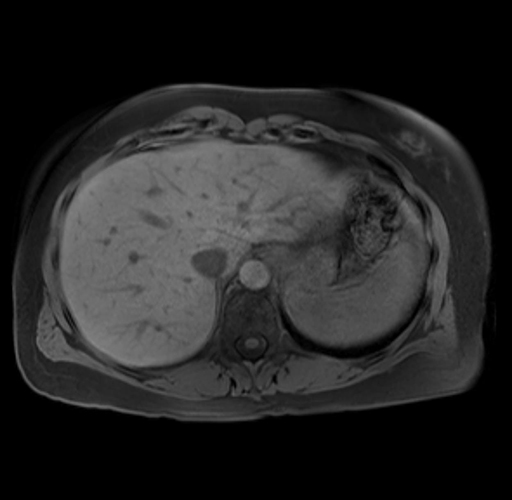

Imaging Analysis

Look through the patient's CT scan to identify any areas of concern for the necessary procedure.

Based on your CT findings, which issue(s) are present and would give reason for "planned slowing down moment(s)" in this case?

Considering a standard distal pancreatectomy procedure, what step(s) of the operation would you do differently in this case?